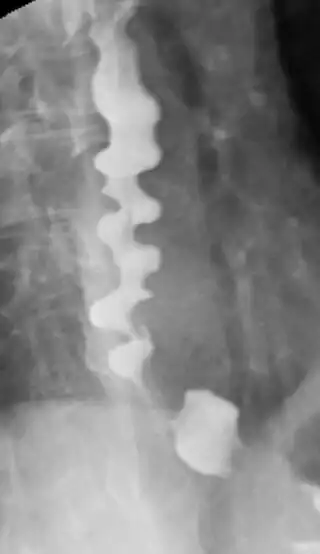

![]() Radiografía en la que se muestra un espasmo esofágico difuso, con su característico aspecto de sacacorchos. | ||

El espasmo esofágico difuso, espasmo esofágico distal, esófago en sacacorchos es una condición médica en la cual se producen contracciones descoordinadas en el esófago. Se cree que es el resultado de diferentes trastornos en la motilidad esofágica. Estos espasmos no propulsan eficientemente el bolo alimenticio al estómago, causando disfagia, regurgitación y dolor en el pecho.[1]